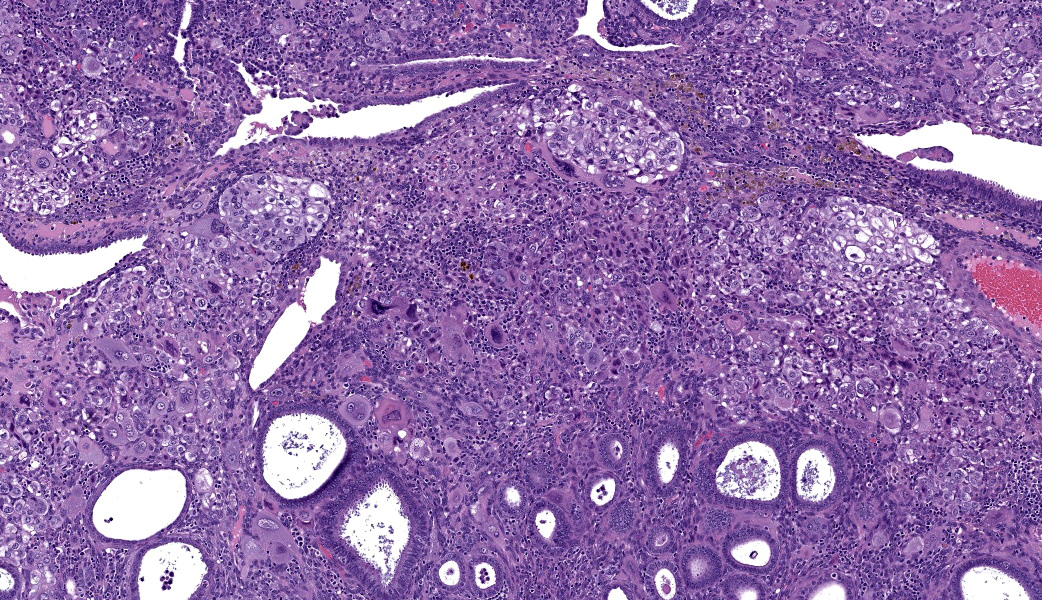

Uterus: Regionally effacing the endometrium, displacing and disrupting the normal glandular and stromal architecture, is a poorly circumscribed, nonencapsulated, infiltrative proliferation of highly pleomorphic round to polygonal neoplastic cells arranged in sheets. The neoplastic proliferation is composed of a biphasic population of uninucleate or multinucleate cells with distinct cell borders, moderate to marked amounts of eosinophilic cytoplasm, and large round vesiculate to finely stippled nuclei and 1-4 variably prominent nucleoli, consistent with a trophoblastic (cytotrophoblasts and syncytiotrophoblasts, respectively) lineage. There are 2 mitotic figures in 10 high power fields (400x). Moderate numbers of lymphocytes and plasma cells are scattered throughout the adjacent endometrial stroma and outer myometrium. Dilated endometrial glands occasionally contain a variable amount of eosinophilic amorphous to basophilic flocculant debris and few macrophages or lymphocytes. Regional erosion of endometrial epithelium is present. The ovary lacks corpora lutea, consistent with sexual immaturity.Slides not provided:

Choriocarcinoma is a neoplasm of trophoblastic lineage that most often arises in women following normal or abnormal pregnancies.1 Diagnostic features include highly pleomorphic, polygonal to round cells with abundant cytoplasm that are both uninucleate (cytotrophoblast or intermediate trophoblast-like) and multinucleate (syncytiotrophoblast) cells, and often a high mitotic rate with metastasis. Morphologic features on histologic evaluation of hematoxylin and eosin-stained uterus from this sexually immature cynomolgus macaque were consistent with choriocarcinoma.In human medicine, choriocarcinoma falls under the umbrella entity of gestational trophoblastic disease. Other neoplasms in this entity include placental site trophoblastic tumor (PSTT) and epithelioid trophoblastic tumor (ETT). PSTTs are composed of a monomorphic population of large, pleomorphic cells derived from implantation-type intermediate trophoblasts. Most cells are uninucleate, but it is not uncommon to see occasional scattered multinucleate cells. ETTs arise from chorionic-type intermediate trophoblasts and present as nests, cords, or solid masses with a monomorphic population of small, round cells.1 Choriocarcinomas tend to have a distinct morphology compared to PSTT and ETT with the presence of uninucleate and multinucleate cells; however, a panel of immunohistochemical markers is commonly used to confirm diagnosis. Characterization with antibodies against hCG, pancytokeratin AE1/AE3, huPL, p63, CD10, PLAPH, and Ki67 provides further support for a diagnosis of choriocarcinoma. These immunohistochemical markers are helpful in distinguishing between PSTT, ETT, and choriocarcinoma (see table).5